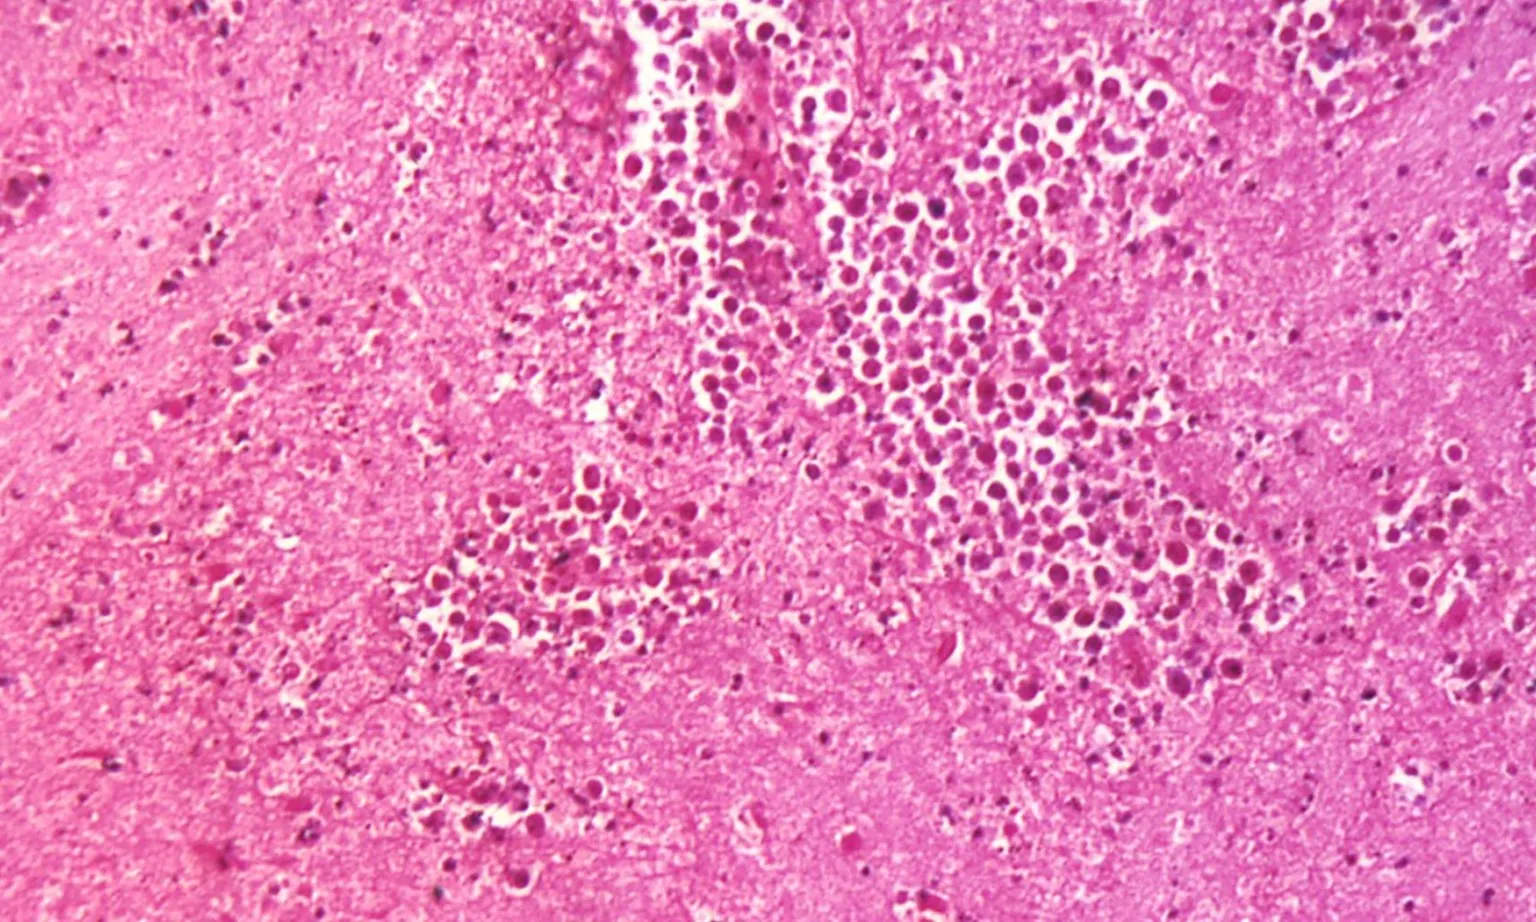

Năm 2022, Kerala ghi nhận 36 ca mắc PAM và 9 ca tử vong. Theo tài liệu của chính quyền bang, PAM là một dạng nhiễm trùng hệ thần kinh trung ương hiếm gặp nhưng cực kỳ nguy hiểm, do loại amip sống tự do trong nước ngọt, hồ và sông gây ra.

Trong hai dạng viêm não do amip, Kerala hiện đang đối mặt với loại nguyên phát – do Naegleria fowleri gây ra. Chính phủ đã triển khai các biện pháp khẩn cấp như khử trùng giếng nước, bể chứa và các khu vực tắm công cộng – nơi người dân có thể tiếp xúc trực tiếp với nguồn nước nhiễm amip.